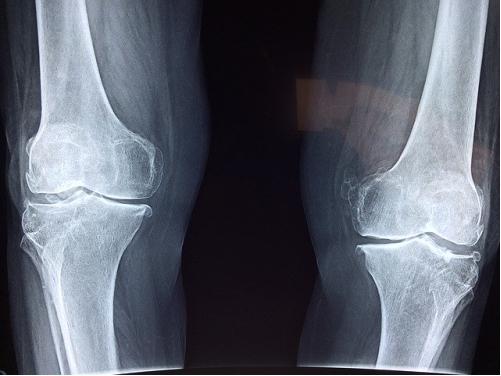

骨关节患病率不低,值得关注

骨关节疾病在我国的发病率非常高,55岁以上人群发病率达到60%,60岁以上患病率超过了80%。60岁及以上老人,几乎都有不同程度的关节疾病。想想都觉得可怕!

引起关节疼痛的原因有很多,若关节退变,比如膝盖退变不是太严重,氨糖针对早期的病变,具有一定的辅助作用。如果关节软骨磨损很严重,甚至已经消失殆尽了,建议到正规医院找专业医生进行治疗哈。对于关节疼痛的人来说,在服用氨糖前,建议先咨询专科医生,确定关节疼的原因是否是退变性关节炎,然后再在医生的指导下服用。